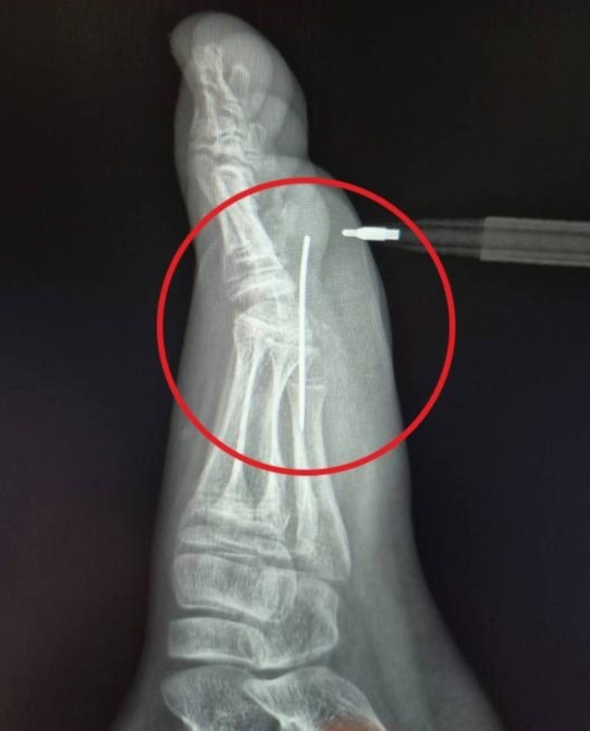

«Мы сделали рентген, который подтвердил наличие инородного тела в стопе, достали иголку специальным инструментом „Москит“. Процедура длилась не больше трех минут и прошла успешно», — рассказал заведующий травматологическим пунктом Артем Лисенков.